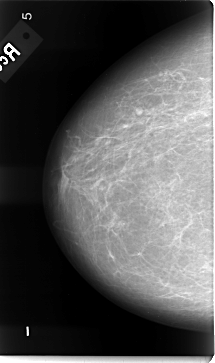

B_3086_1.RIGHT_CC

RIGHT_CC LINES 4712 PIXELS_PER_LINE 2792 BITS_PER_PIXEL 12 RESOLUTION 50 NON_OVERLAY